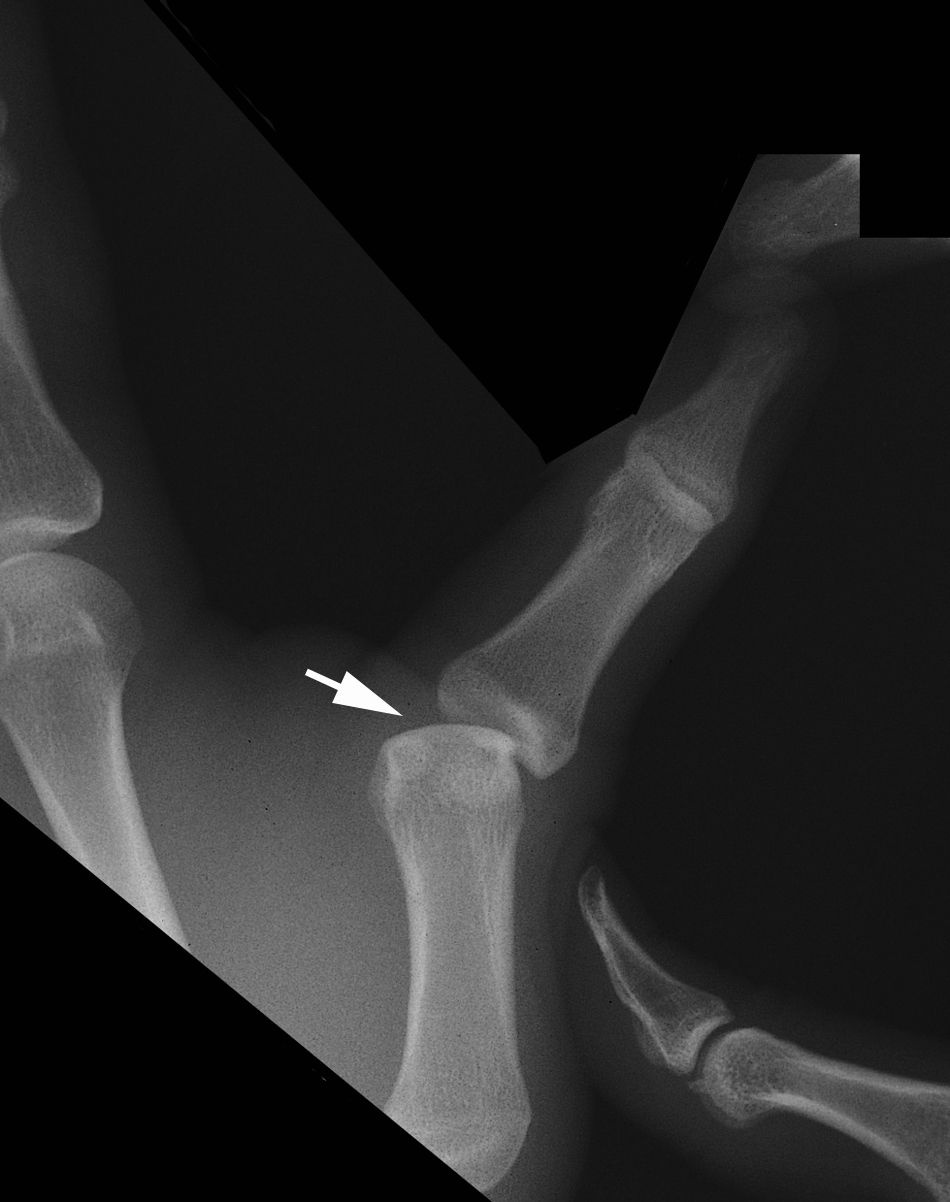

Thumb proximal phalanx avulsion fracture Image Avulsion Fracture Thumb Is this the patient’s dominant hand? B, reverse bennett fracture (at the base of. Thumb collateral ligament injuries, most commonly ulnar collateral (ucl), are athletic injuries that lead to a decrease in effective thumb. Fractures of the thumb are usually associated with local bruising, swelling, pain and loss of function, with or without deformity. How crucial is optimal hand function. Avulsion Fracture Thumb.

xray showing an avulsion fracture of the proximal phalanx of the thumb Avulsion Fracture Thumb B, reverse bennett fracture (at the base of. Summary diagram of the hand and wrist with labeled sites of the most common avulsion injuries: A, bennett fracture (at the base of the thumb); Thumb collateral ligament injuries, most commonly ulnar collateral (ucl), are athletic injuries that lead to a decrease in effective thumb. Is this the patient’s dominant hand? Fractures. Avulsion Fracture Thumb.